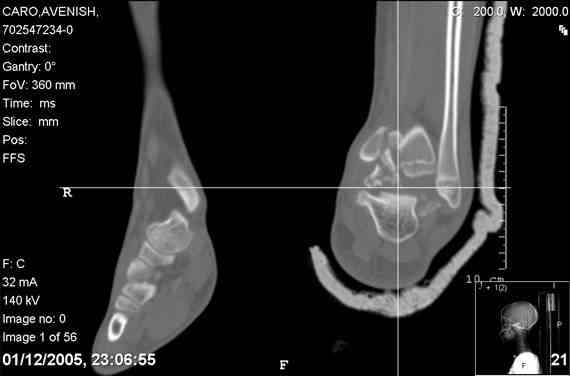

ya by popytalsya sobrat talus anatomichno,seichas pozdno operirovat iz za oteka,po etomy distrakziya apparatom budet optmalna.Posyalu vam podobyai moi sluchai.

14 years old girl

Fall from height ( 3rd floor)

Compressed fractures of L1-L2

Fx of orbital bone

Mark, судя по снимкам в день поступления произведен А.В.Ф., а остеосинтез ч-з какое время произведен?, остеосинтез произвели открытым способом?( на снимке п/о рубцы).

aparat postavlen v den postupleniya,rastaynuli, vpravili zakryto naskolko vozmoghno, a kogda otek spal sdelali otkrytoe vpravlenie.Teryat tut nechego, moghno tolko uluchshit.